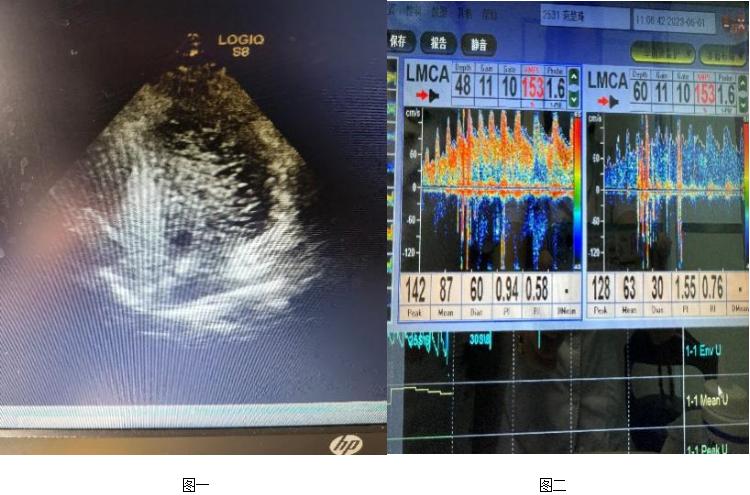

我院神经内二科主任钟水生接诊后,为患者完善专科查体,结果都正常。入院后完善右心声学造影:静息状态下3-6个周期内,房水平右向左分流3级,Valsalva动作释放时,房水平3-6个周期内左房、左室可见持续性浓密造影剂气泡回声,静息状态及Valsalva动作房水平右向左分流均3级,考虑存在卵圆孔未闭可能性大(图一)。TCD发泡试验阳性,支持右向左分流(图二)。心脏彩超:心脏未见异常。进一步完善头颅MR平扫+半球动脉(MRA) 示部分空蝶鞍,右侧大脑前动脉A1段发育不良(图三)。